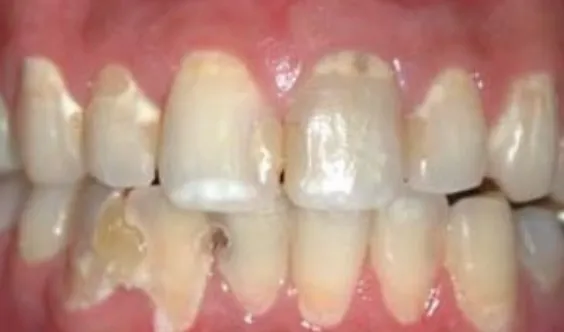

• ところどころ虫歯になっている歯列

ジュースを常時飲むと

残念なお口に